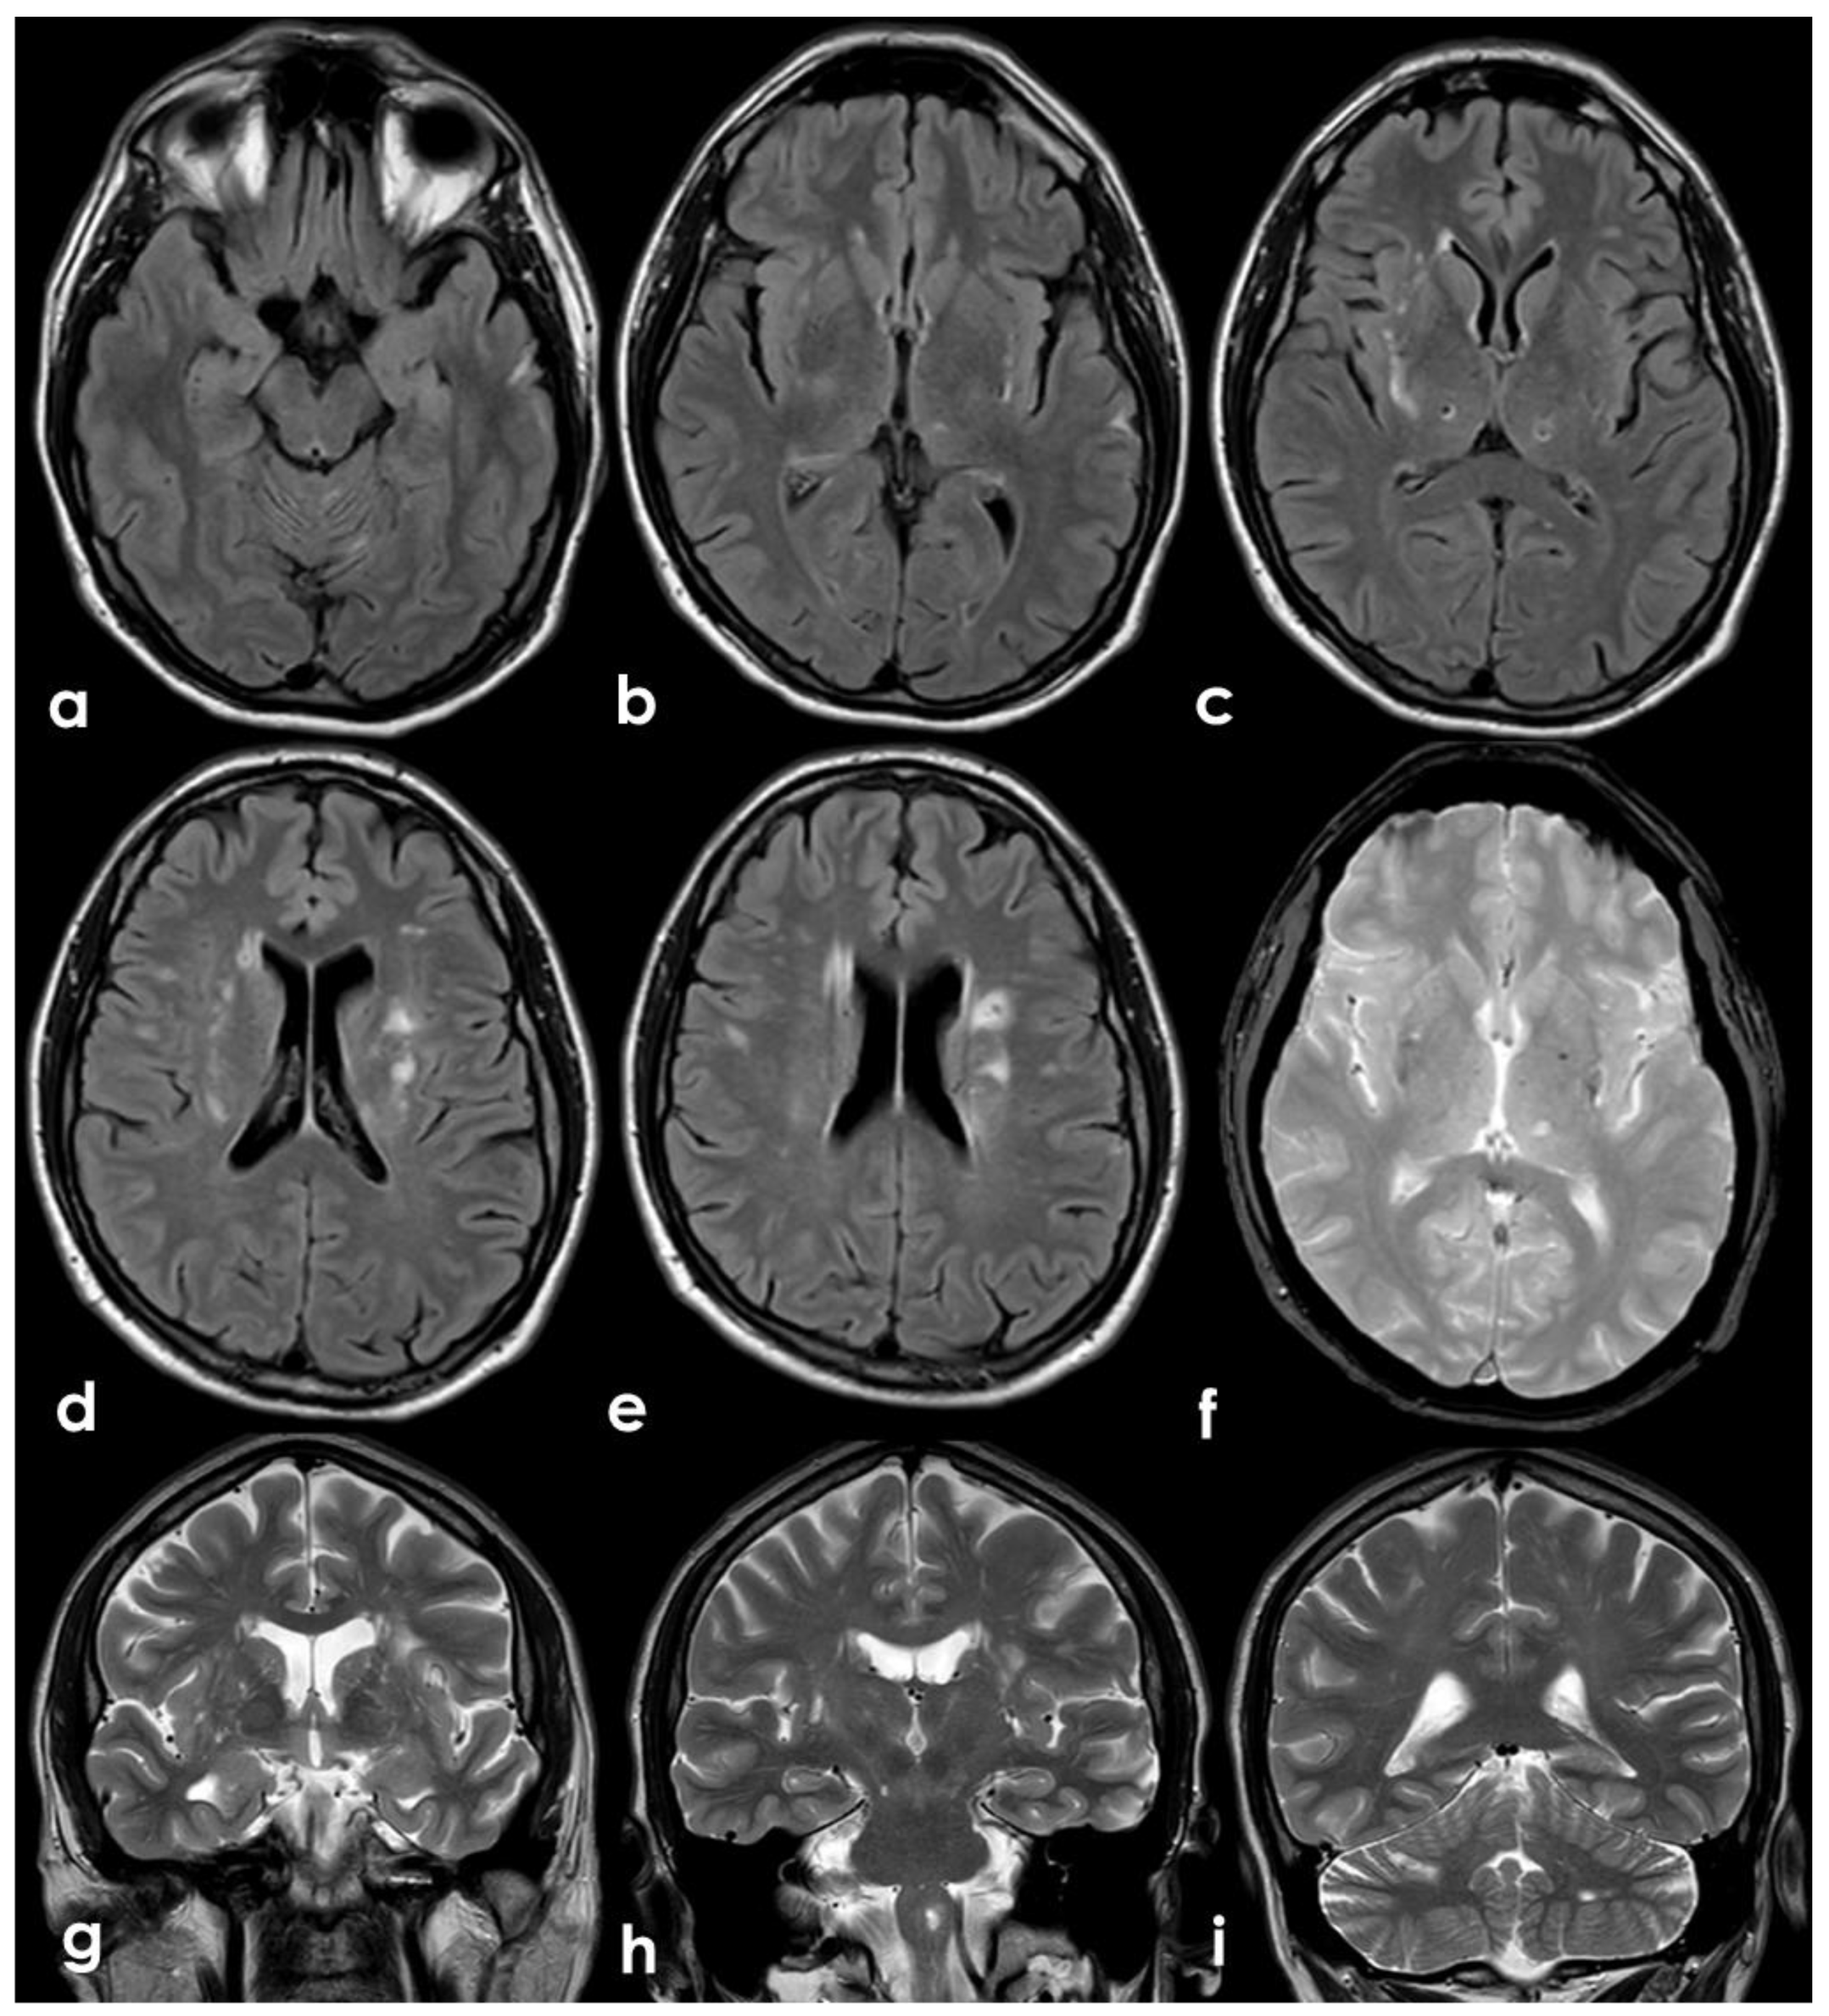

A 46-year-old man was referred to the Emergency Department (ED) in the afternoon because of unsteadiness, vertigo and nausea, reporting the awareness of the symptoms at awakening, around ten hours before the consultation; his last time well was almost 24 h before. His past medical history was notable for two episodes of head concussion without clinical consequences and brain lesions on CT imaging, the recent finding of increased value of glycated hemoglobin and a long-lasting IDA, erratically treated with iron oral supplementation. The first blood laboratory assessment in ED confirmed the microcytic anemia without other relevant findings: hemoglobin 8.3 g/dL (normal range 14.0–17.5 g/dL), RBCs 4.26 × 106/µL (normal range 4.50–6.00 millions/µL), hematocrit 28.6% (normal range 40.0–52.0%), MCV 67.3 fL (normal range 80.0–95.0 fL), MCH 19.5 pg (normal range 26.0–32.0 pg), MCHC 28.9 g/dL (normal range 32.5–36.0 g/dL), platelets 211 × 1000 µL (normal range 150–400 × 1000/µL), fibrinogen 188 mg/dL (normal range 181.0–384.0 mg/dL), D-dimer 2485 ng/mL (normal range 10–500 ng/mL), regular liver and kidney functions, absence of electrolytic disturbances and normal inflammatory markers. The initial neurological examination was remarkable for impaired alertness (psychomotor slowness, tendency to fall asleep), dysarthria and left limbs ataxia with a global National Institute of Health Stroke Scale (NIHSS) score of 11. The patient underwent an unenhanced brain CT scan, whose findings were significant for multiple subcortical hypodensities in both cerebellar hemispheres and vermis, which was highly suggestive of subacute ischemic lesions in the territory of bilateral posterior inferior cerebellar artery (PICA) and left superior cerebellar artery (SCA) (Figure 1).

Figure 1. Brain CT performed at the admittance to the ED. From a to d: ascending axial CT slices of the posterior cranial fossa, showing bilateral subcortical multiple rounded hypodensities in the cerebellar white matter (a) in PICA territory with left side prevalence (b,c) and a similar hyperintense lesion in the superior part of vermis (bd) and in the left anterior lobe of the cerebellum, supplied by the superior cerebellar artery (SCA).